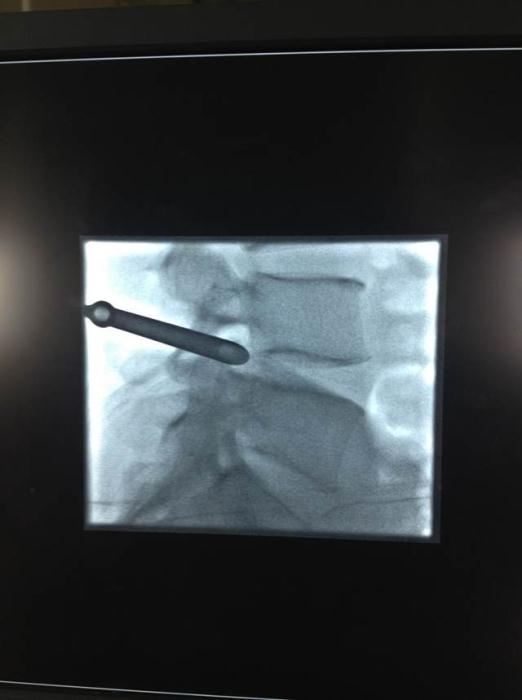

A术前

图1:A术前

图2:A术中

如今,在疼痛病房经常看到患者脸上洋溢着满意的笑容。占恭豪主任说,上述三位患者的腰椎都是巨大突出,张先生的突出物似门帘下垂;李先生的腰椎突出物似尾巴上翘,陈公公的是两节的腰椎巨大突出,神经都严重的受压,导致日常活动明显受限,生活质量严重下降。